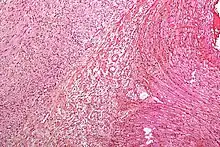

Hypoesthesia primarily results from damage to nerves, and from blockages in blood vessels, resulting in ischemic damage to tissues supplied by the blocked blood vessels. This damage is detectable through the use of various imaging studies. Damage in this way is caused by a variety of different illnesses and diseases. A few examples of the most common illnesses and diseases that can cause hypoesthesia as a side effect are as follows: